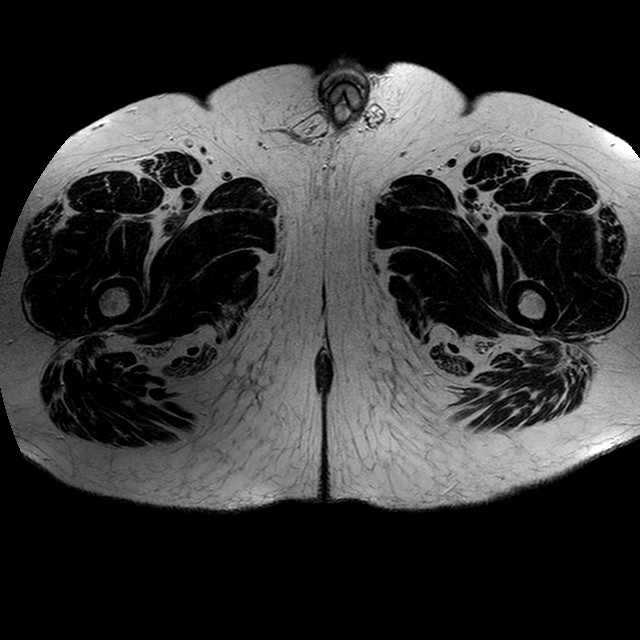

Esami: RMN BACINO

T2w TSE

Evidenti e simmetriche alterazioni osteofitosiche in regione coxo femorale con riduzione delle rime articolari. Degenerazione completa del cercine glenoideo. Non attuali segni di versamento articolare. Non segni di edema osseo che escludono attuale algodistrofia od osteonecrosi. Lieve e simmetrica riduzione del trofismo della muscolatura glutea.